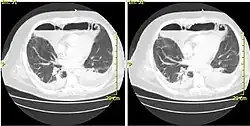

Acute mediastinitis can be confirmed by contrast x-rays since most cases of acute mediastinitis are due to esophageal perforation. Other studies that can be used include endoscopic visualization, Chest CT scan with oral and intravenous contrast.

With regards to CT Imaging, the extent of involvement of the mediastinum can be evaluated. Therefore, acute mediastinitis can be classified into three categories:[9]

Chronic

Most cases of granulomatous mediastinitis (75%) are incidentally found on chest x-rays which show a mediastinal mass, or widening of the mediastinum.[6]